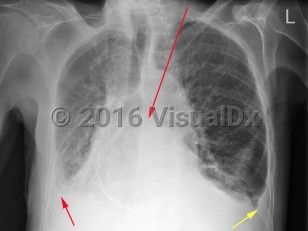

- Airway / Breathing: Often, positive end-expiratory pressure (PEEP) is required via a continuous positive airway pressure (CPAP) or bilevel positive airway pressure (BiPAP) machine for increased work of breathing, hypoxia, or evidence of pulmonary edema on examination or imaging.